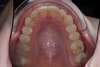

Décalage maxillo mandibulaire traité par gouttières

C-Début 3